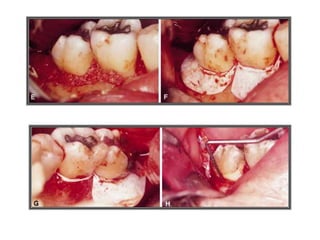

TRATAMENTO DAS LESÕES

ENDOPERIODONTAIS

Rizectomia

DEL RIO, 1996

Rizectomia

ODONTOSSECÇÃO